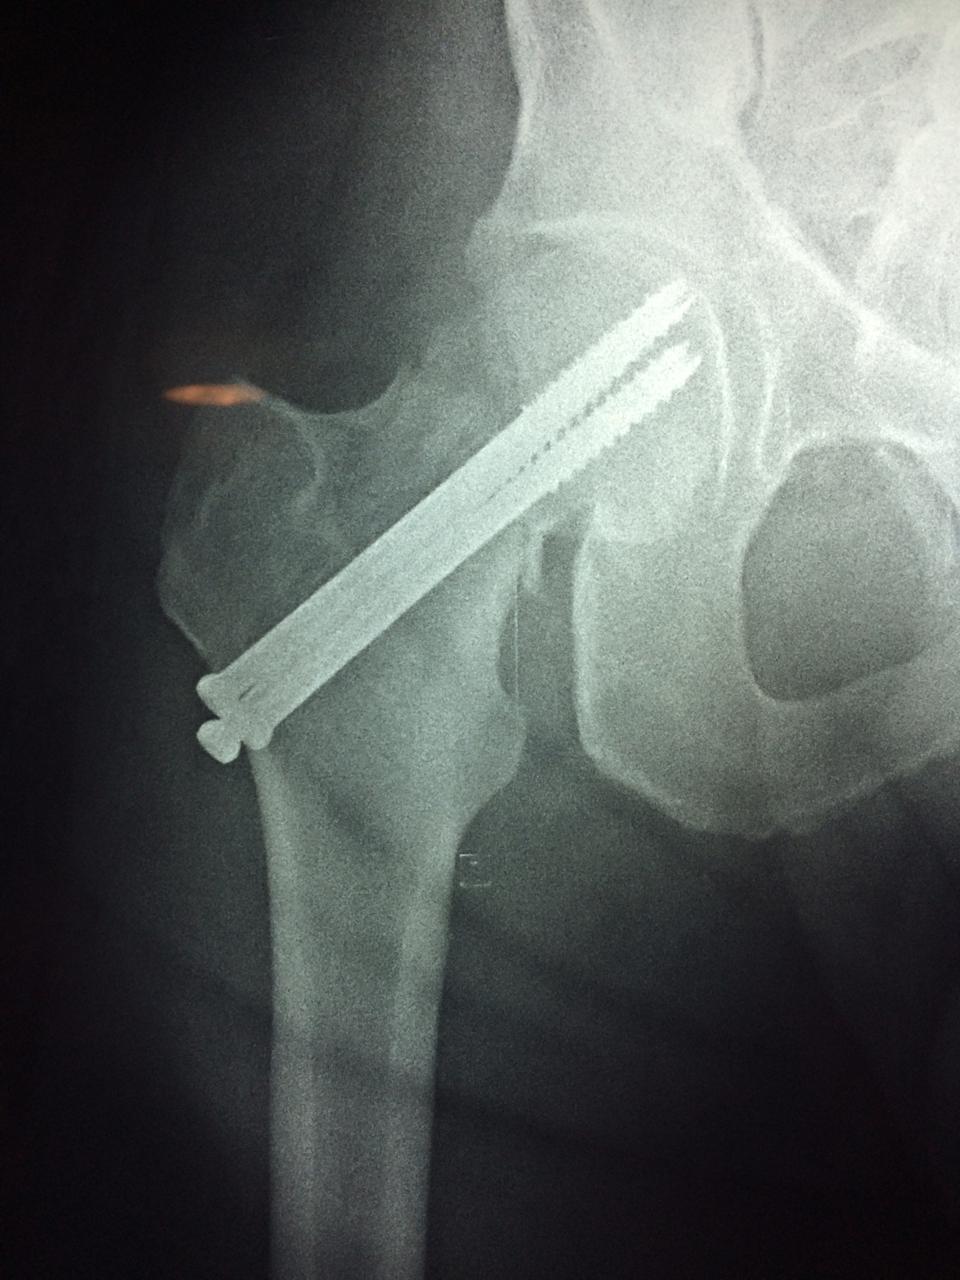

A menudo se recomienda la cirugía para reparar la fractura debido a dichos riesgos.